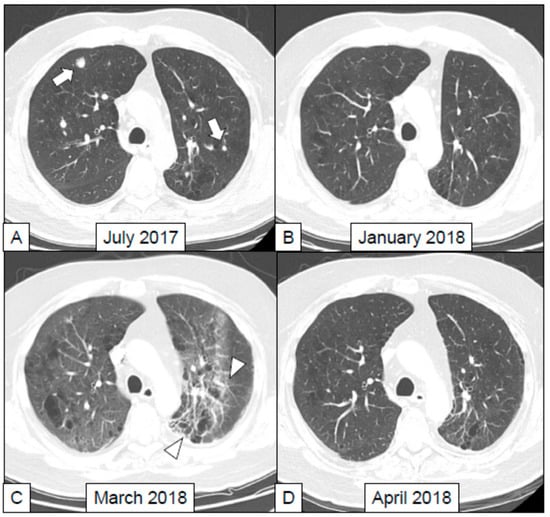

- Kanai, O.; Nakatani, K.; Fujita, K.; Okamura, M.; Mio, T. Concurrence of nivolumab-induced interstitial lung disease and cancer invasion. Respirol. Case Rep. 2017, 5, e00257. [Google Scholar] [CrossRef] [PubMed]

- Nishino, M.; Ramaiya, N.H.; Awad, M.M.; Sholl, L.M.; Maattala, J.A.; Taibi, M.; Hatabu, H.; Ott, P.A.; Armand, P.F.; Hodi, F.S. PD-1 Inhibitor-Related Pneumonitis in Advanced Cancer Patients: Radiographic Patterns and Clinical Course. Clin. Cancer Res. 2016, 22, 6051–6060. [Google Scholar] [CrossRef] [PubMed]